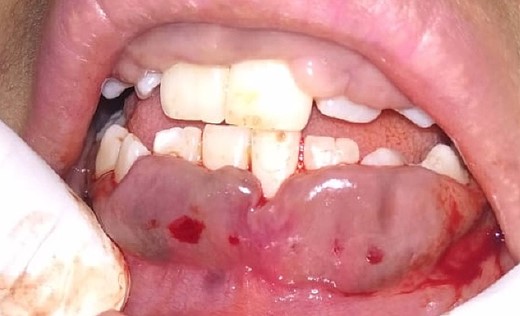

Intraoral examination shows generalized puffiness and swollen gingiva, mainly in the upper and lower anterior region covering two-third of the entire teeth, the color of the gingiva was bluish red, which bleeds on slight provocation as well as on mastication of hard food. (Fig. 1).